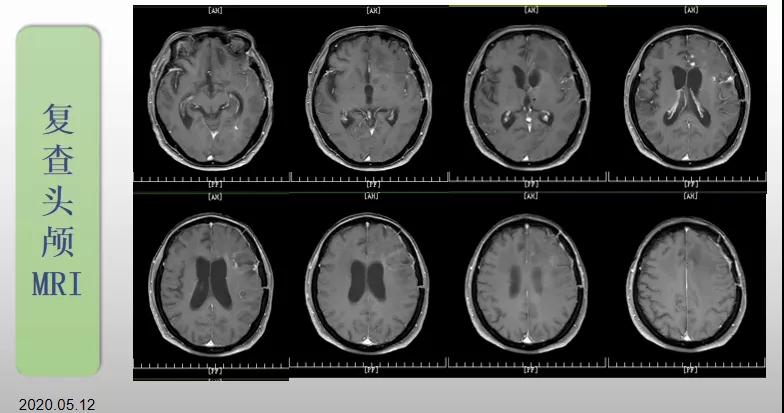

綜合治療 電場治療助70歲患者回歸正常生活

70歲的郝女士去年曾在外院查出“左額島葉”膠質(zhì)母細胞瘤(WHO Ⅳ級),并做了左側(cè)額島葉占位性病變切除術(shù)。術(shù)后進行了同步放化療。由于治療條件有限,郝女士慕名來到我院就診。賀世明主任率領醫(yī)護團隊立即為郝女士進行了全面的檢查,決定為其進行綜合治療 電場治療。經(jīng)過三個多月的綜合治療,患者復查頭顱MRI病變較前明顯縮小。出院時,郝女士神志清醒,睡眠飲食正常,說話很流利。“我是躺著進來的,現(xiàn)在不用人攙扶,自己就可以走出病房了。”郝女士拉著醫(yī)護人員的手說。